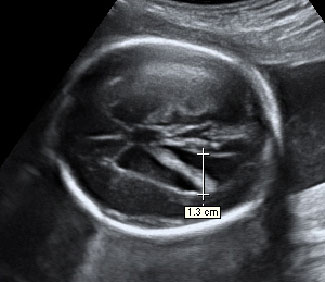

En la ecografía en 4D de un feto de 18 semanas de embarazo se ve la cara ya armonizada: las orejas y los ojos que en un principio estaban desplazados, ya se encuentran en su lugar, lo que le da una imagen mucho más "humana".

Ecografía de la cara de un bebé de 18 semanas